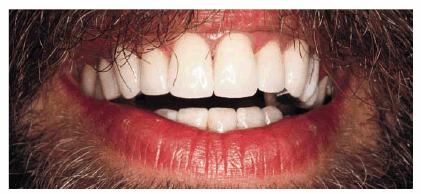

PROBLEM: This 38-year-old store owner presented with crowded and

discolored maxillary and mandibular teeth (Figures 24-7A, and 24-7B). Although orthodontic treatment was suggested as ideal

treatment, he elected a compromise that consisted of bonding the mandibular and

RESULT: The resulting smile with straighter and lighter teeth (Figures 24-7H, and 24-7I) was most appreciated by the patient.

Figure 24-7H: Pretreatment smile.

Figure 24-7I: Post-treatment smile with six maxillary full porcelain crowns and four mandibular incisors with bonded composite resins.